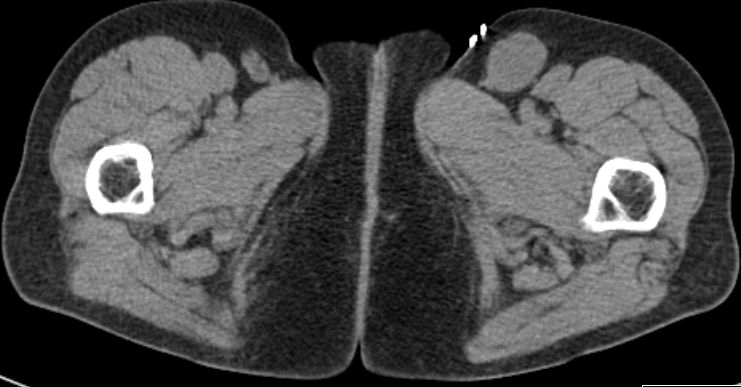

72-jähriger Mann mit Verdacht auf

Hernia inguinalis rechts. PE: diffuses großzelliges B-Zellymphom.![]() |

Befall der Nl. iliaca externa![]() | ||